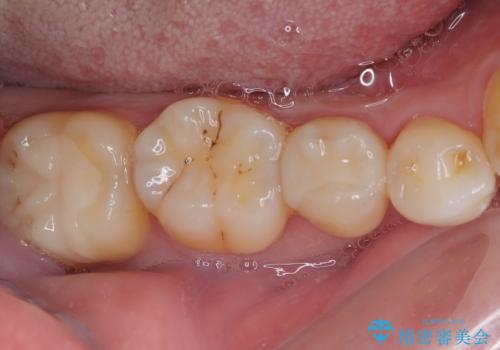

- 銀歯やむし歯でものが挟まるところが気になるとのことで来院された患者様です。

左上の奥歯は神経が失活しており、根管治療が必要な状態でした。

その他は銀歯のインレー(部分的な詰め物)が装着されており、それらはむし歯を除去した後にセラミックインレーにて修復治療を行い、左下と根管治療を行う左上の奥歯はオールセラミッククラウンにて補綴治療を行うこととしました。